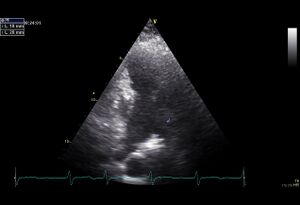

| Plax by tilted (Plax PV) | PSax Ao |

| Suprasternal apd (color doppler) | Dilated apd (Plax PV) |